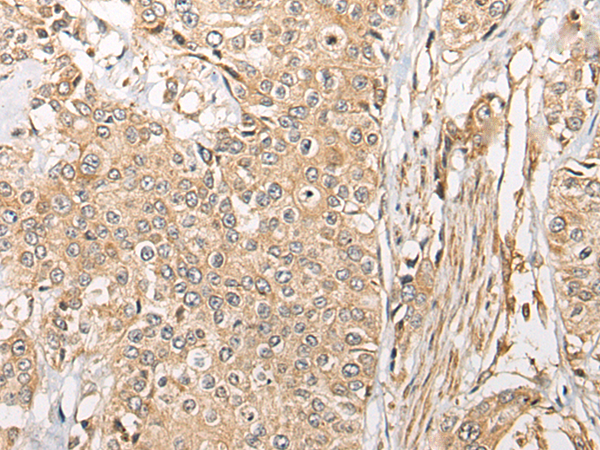

分类: 科研抗体货号: P09413别名:应用: IHC反应种属: Human, Mouse, Rat